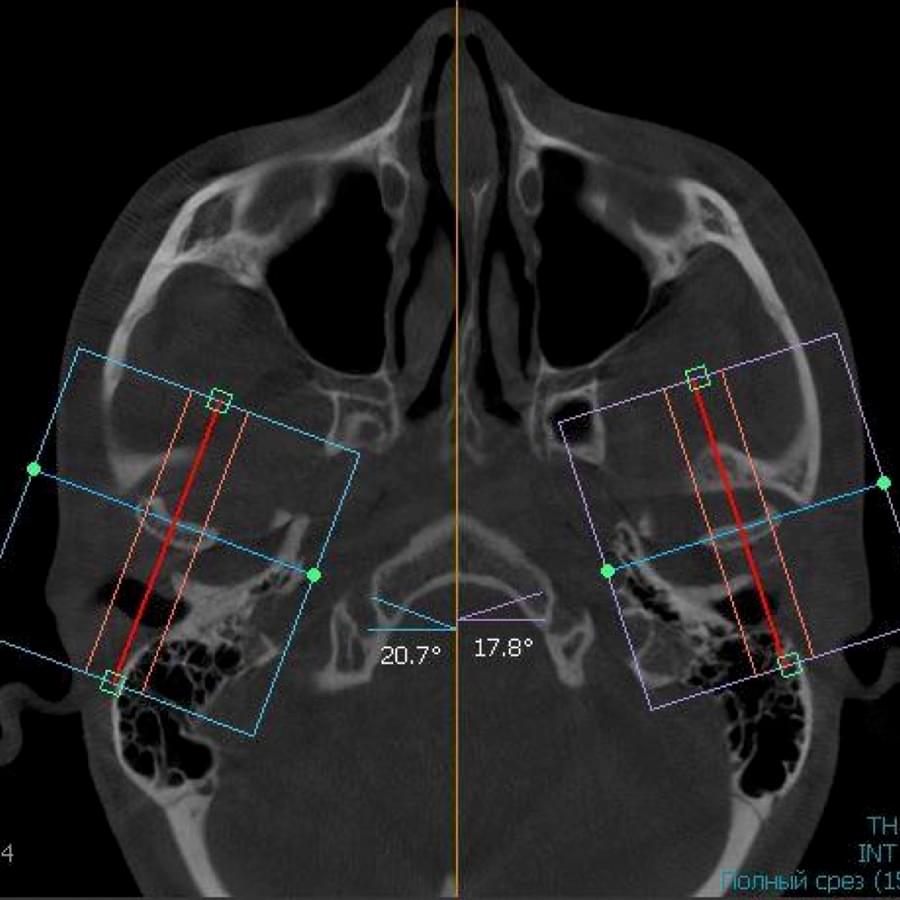

3D цефалометричний аналіз є сучасною технологією, яка дозволяє отримувати точніші,

комплексніші та надійніші дані про зубну та скелетну структуру. Ця технологія може стати

великим кроком в перед для ортодонтів, які хочуть забезпечити найкраще можливе лікування

своїх пацієнтів.

Основні переваги 3D цефалометричного аналізу:

Точність: 3D цефалометричний аналіз забезпечує точніше визначення розмірів та відстаней між

зубами та кістковими структурами.

Комплексність: ця технологія дозволяє отримувати детальні дані про різні структури, такі як

кістка та м'язи, що дозволяє ортодонтам докладніше досліджувати деякі патології та планувати

лікування.

Надійність: 3D цефалометричний аналіз дозволяє отримувати надійніші результати, оскільки

виключає можливість помилок, пов'язаних зі спотворенням або перекриттям зображень.